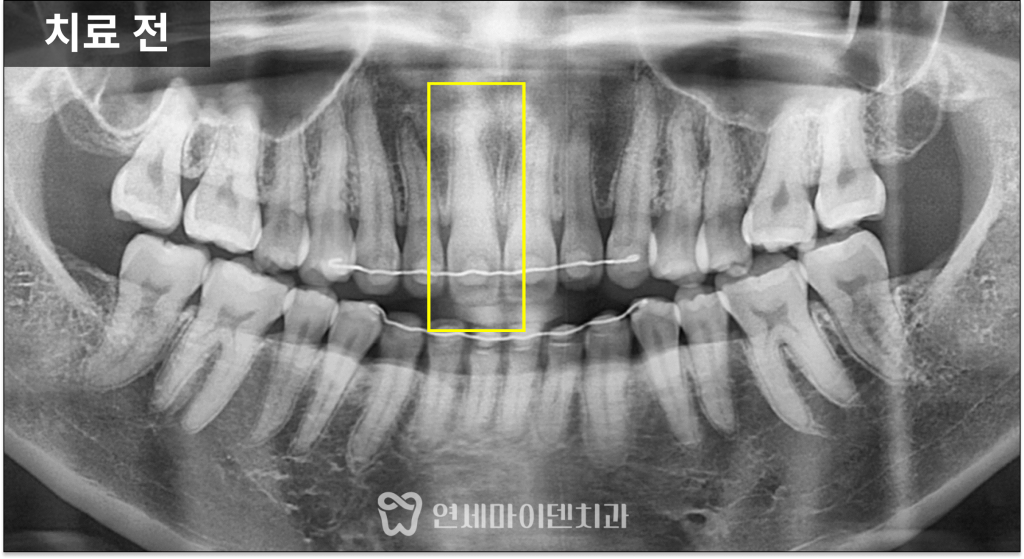

이번 케이스에서는

냉검사와 전기 검사 모두에서

반응이 나타나지 않아

신경이 이미 괴사된 상태로 판단했습니다.

이때 엑스레이상 뿌리 끝에

뚜렷한 염증이 보이지 않는 경우도 많습니다.